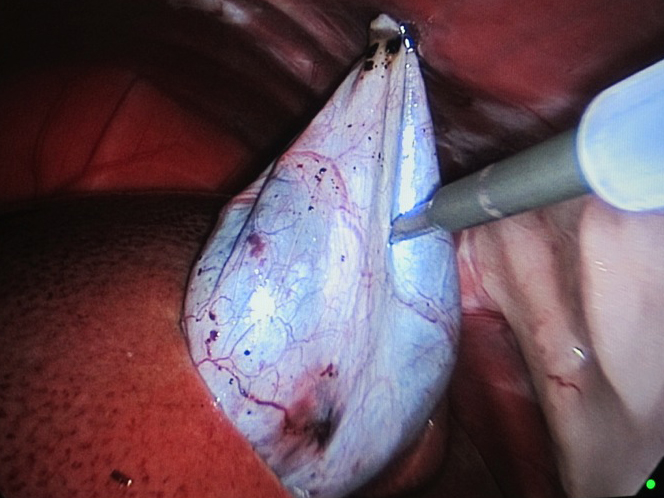

体の外に出すためお腹の中で袋に入れていきます。

このときに胆嚢と一緒にクリップやガーゼも回収します。そしてお腹の中をきれいにしていきます。

回収袋にいれて体外に摘出していきます。